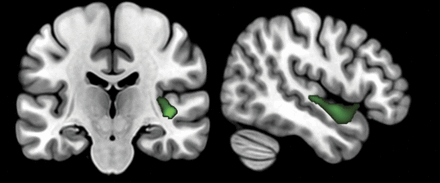

封面图片:灰质f0范围的相关语义变异患者原发性进行性失语和语义行为变异额颞叶痴呆。程式化的凯特林阿曼•兰姆、高级数字多媒体/图形协调员。看到页面e825